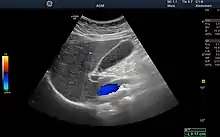

Ultrasound

Medical ultrasound uses high frequency broadband sound waves in the megahertz range that are reflected by tissue to varying degrees to produce (up to 3D) images. This is commonly associated with imaging the fetus in pregnant women. Uses of ultrasound are much broader, however. Other important uses include imaging the abdominal organs, heart, breast, muscles, tendons, arteries and veins. While it may provide less anatomical detail than techniques such as CT or MRI, it has several advantages which make it ideal in numerous situations, in particular that it studies the function of moving structures in real-time, emits no ionizing radiation, and contains speckle that can be used in elastography. Ultrasound is also used as a popular research tool for capturing raw data, that can be made available through an ultrasound research interface, for the purpose of tissue characterization and implementation of new image processing techniques. The concepts of ultrasound differ from other medical imaging modalities in the fact that it is operated by the transmission and receipt of sound waves. The high frequency sound waves are sent into the tissue and depending on the composition of the different tissues; the signal will be attenuated and returned at separate intervals. A path of reflected sound waves in a multilayered structure can be defined by an input acoustic impedance (ultrasound sound wave) and the Reflection and transmission coefficients of the relative structures.[13] It is very safe to use and does not appear to cause any adverse effects. It is also relatively inexpensive and quick to perform. Ultrasound scanners can be taken to critically ill patients in intensive care units, avoiding the danger caused while moving the patient to the radiology department. The real-time moving image obtained can be used to guide drainage and biopsy procedures. Doppler capabilities on modern scanners allow the blood flow in arteries and veins to be assessed.